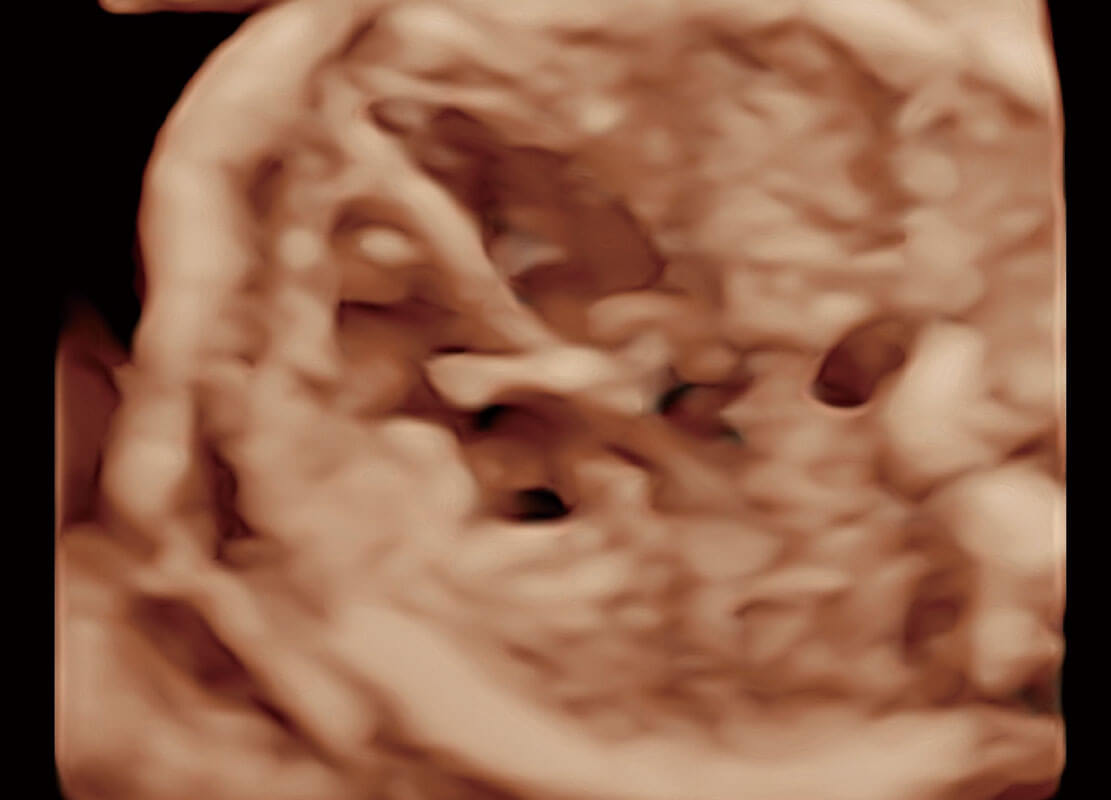

胎心筛查

P60搭载一系列胎儿心脏成像技术,实现精细的胎儿心脏评估。

• 胎心容积成像